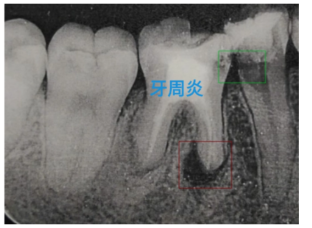

X光病癥識(shí)別算法利用計(jì)算機(jī)視覺和深度學(xué)習(xí)技術(shù)對(duì)X光影像進(jìn)行自動(dòng)分析,幫助醫(yī)生快速準(zhǔn)確地識(shí)別各種疾病。這種技術(shù)可以顯著提高診斷效率和準(zhǔn)確性,并為患者提供更好的治療方案。

通過深度學(xué)習(xí)技術(shù)對(duì)X光、CT、MRI、超聲波等醫(yī)學(xué)影像進(jìn)行自動(dòng)分析,幫助醫(yī)生快速準(zhǔn)確地識(shí)別病變區(qū)域。